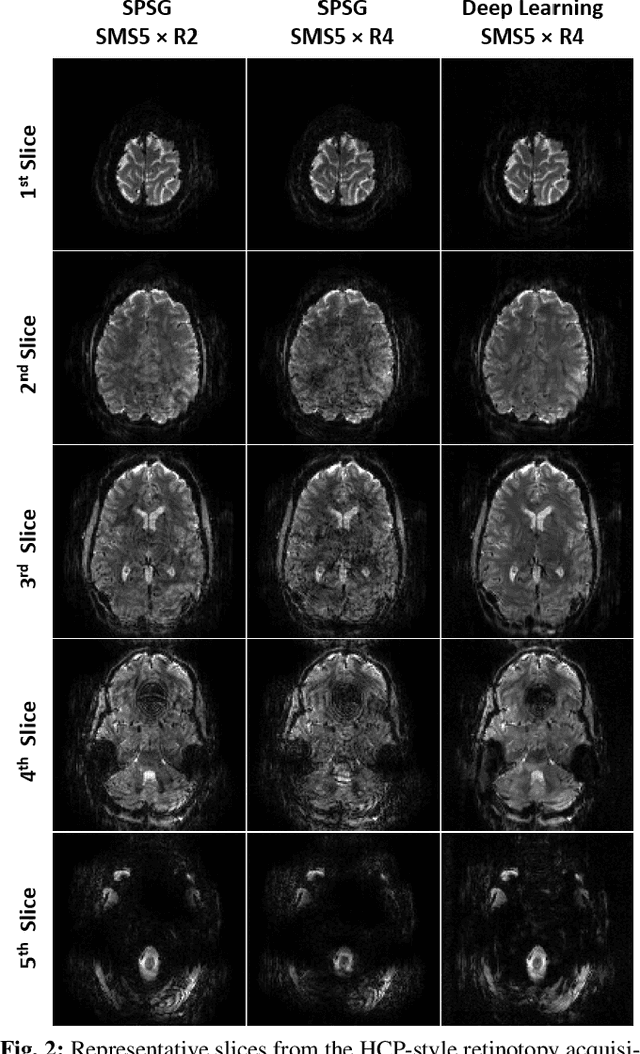

Abstract:High spatial and temporal resolution across the whole brain is essential to accurately resolve neural activities in fMRI. Therefore, accelerated imaging techniques target improved coverage with high spatio-temporal resolution. Simultaneous multi-slice (SMS) imaging combined with in-plane acceleration are used in large studies that involve ultrahigh field fMRI, such as the Human Connectome Project. However, for even higher acceleration rates, these methods cannot be reliably utilized due to aliasing and noise artifacts. Deep learning (DL) reconstruction techniques have recently gained substantial interest for improving highly-accelerated MRI. Supervised learning of DL reconstructions generally requires fully-sampled training datasets, which is not available for high-resolution fMRI studies. To tackle this challenge, self-supervised learning has been proposed for training of DL reconstruction with only undersampled datasets, showing similar performance to supervised learning. In this study, we utilize a self-supervised physics-guided DL reconstruction on a 5-fold SMS and 4-fold in-plane accelerated 7T fMRI data. Our results show that our self-supervised DL reconstruction produce high-quality images at this 20-fold acceleration, substantially improving on existing methods, while showing similar functional precision and temporal effects in the subsequent analysis compared to a standard 10-fold accelerated acquisition.

Abstract:Functional MRI (fMRI) is commonly used for interpreting neural activities across the brain. Numerous accelerated fMRI techniques aim to provide improved spatiotemporal resolutions. Among these, simultaneous multi-slice (SMS) imaging has emerged as a powerful strategy, becoming a part of large-scale studies, such as the Human Connectome Project. However, when SMS imaging is combined with in-plane acceleration for higher acceleration rates, conventional SMS reconstruction methods may suffer from noise amplification and other artifacts. Recently, deep learning (DL) techniques have gained interest for improving MRI reconstruction. However, these methods are typically trained in a supervised manner that necessitates fully-sampled reference data, which is not feasible in highly-accelerated fMRI acquisitions. Self-supervised learning that does not require fully-sampled data has recently been proposed and has shown similar performance to supervised learning. However, it has only been applied for in-plane acceleration. Furthermore the effect of DL reconstruction on subsequent fMRI analysis remains unclear. In this work, we extend self-supervised DL reconstruction to SMS imaging. Our results on prospectively 10-fold accelerated 7T fMRI data show that self-supervised DL reduces reconstruction noise and suppresses residual artifacts. Subsequent fMRI analysis remains unaltered by DL processing, while the improved temporal signal-to-noise ratio produces higher coherence estimates between task runs.